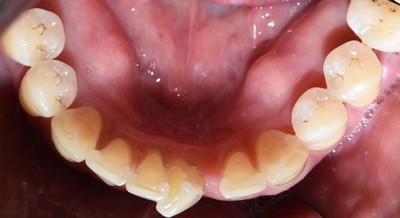

[2020년 3월]

6개월만에 교정장치가 보이지 않는 비밀스런 설측교정으로

요렇게 완료되고 유지장치까지 완성되었습니다.